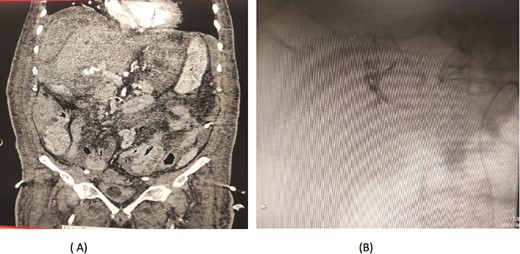

A 76-year-old male underwent distal gastrectomy with D2 lymph node dissection for gastric cancer. On the 27th postoperative day, he developed massive upper gastrointestinal (UGI) bleeding, which was confirmed by an upper gastrointestinal endoscopy (UGIE) showing large clots. A contrast-enhanced CT angiogram revealed a pseudoaneurysm arising from the common hepatic artery (CHA) and proper hepatic artery (HA). Angioembolization was promptly performed using two coils, successfully controlling the bleeding. Despite this intervention, the patient experienced re-bleeding 12 days later. Repeat UGIE again demonstrated massive clots, and CT angiography confirmed the presence of a pseudoaneurysm at the CHA. A second angioembolization was conducted using four coils, which successfully halted the bleeding. The patient’s condition stabilized, and he was closely monitored with no further complications noted (Fig. 5).

Case 5. (A) Angiogram shows a pseudoaneurysm at common hepatic artery and another at hepatic artery proper. (B) Common hepatic artery was selected and embolization performed with two coils and gelfoam